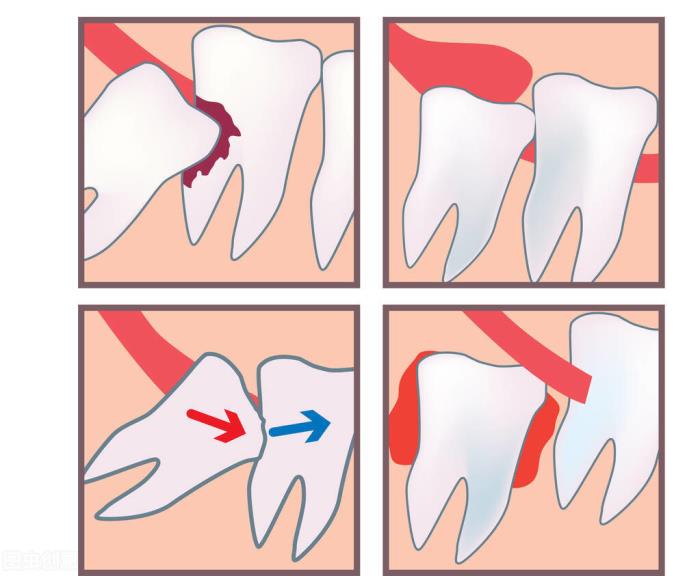

蛀牙的智齿。

如果智齿龋坏了,除了咬合面简单的龋坏且蛀的不深可以补,像邻面龋是需求很好的技术才能补,如果蛀的深还要进行根管治疗。所以一律建议直接拔掉,以绝后患。

侵犯到邻牙的智齿。

这类智齿大多数直接是不知道的,只能由医生拍牙片来检查确诊。由于智齿萌出的空间不足,导致智齿倾倒在第二大臼齿上,出现清洗不易、牙齿吸收的现象,会导致患者出现不适、牙疼。因此也是主张拔掉的!